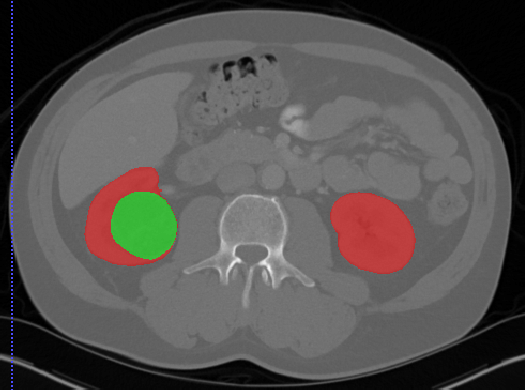

3D-IRCADB

| 3D-IRCADb 01 02 | 肝脏/肝肿瘤 | 分割 | CT | 20+2 | surface mesh | dcm | CC |

3D-IRCADb是比较早的一个数据集,有两个子集,分别包含20组和2组CT片子。